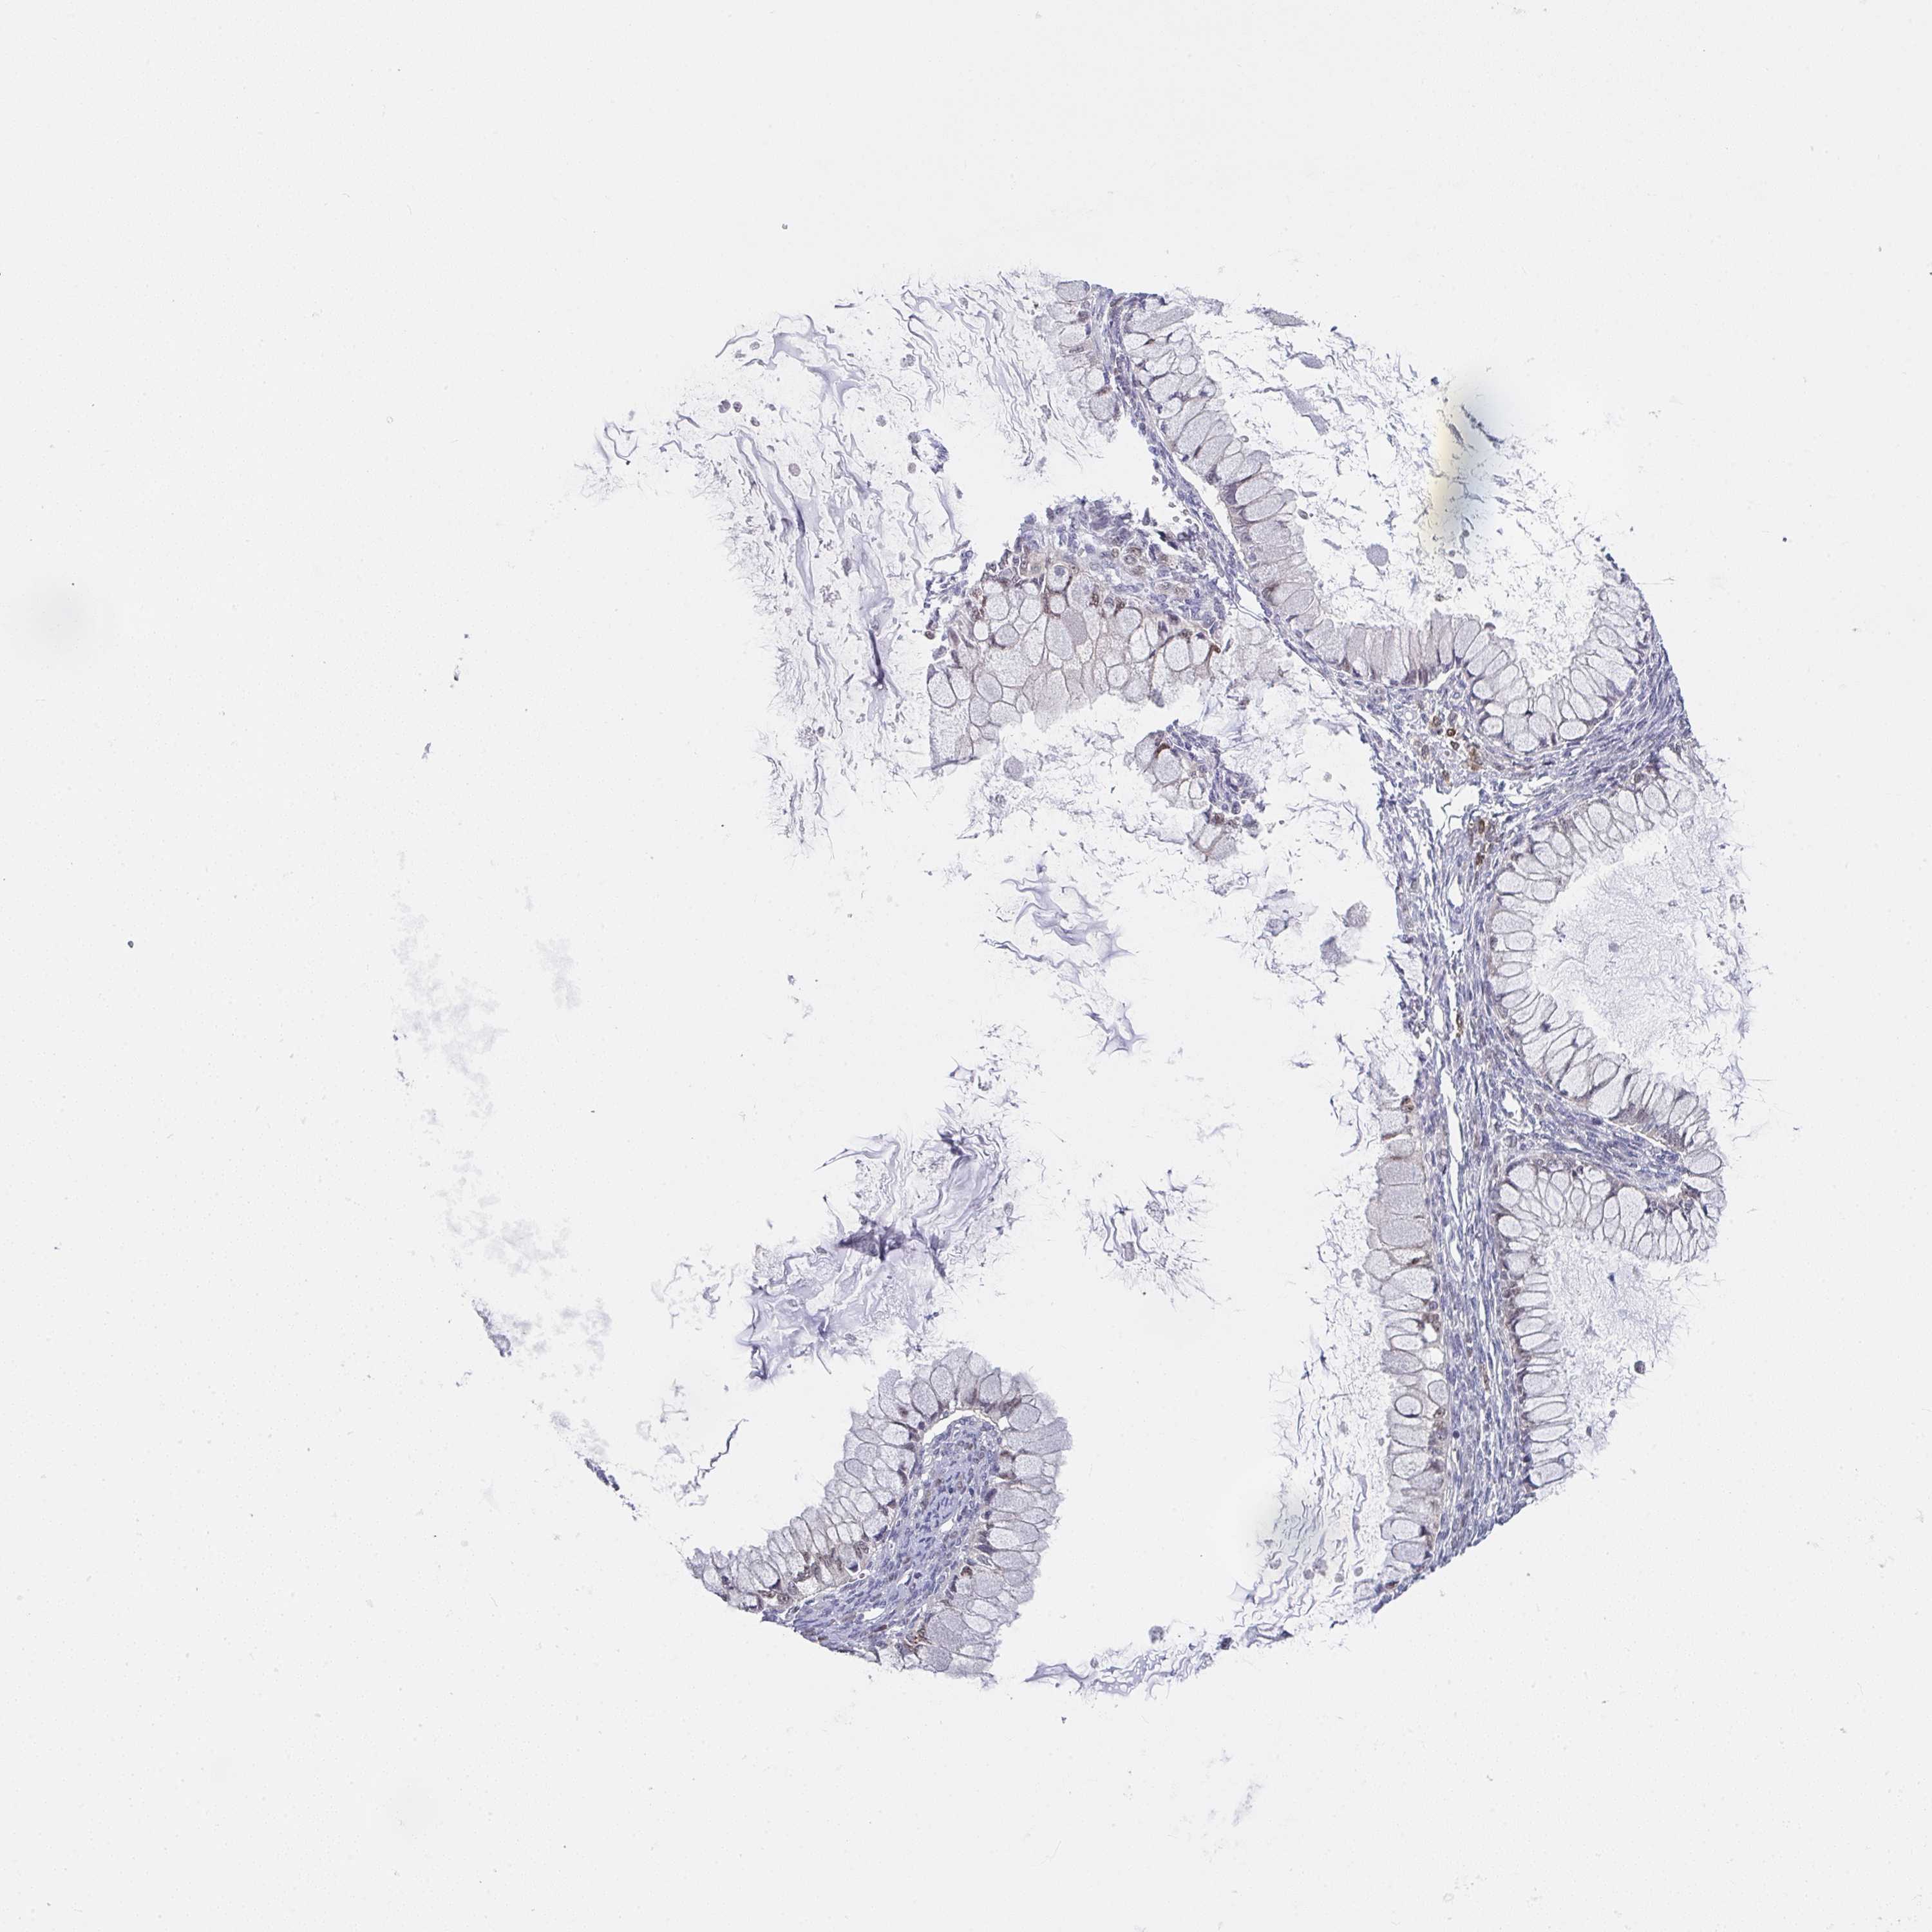

OVARIAN CANCER - Protein expressioni

A mouse-over function shows sample information and annotation data. Click on an image to view it in a full screen mode. Samples can be filtered based on level of antibody staining by selecting one or several of the following categories: high, medium, low and not detected. The assay and annotation is described here.

Note that samples used for immunohistochemistry by the Human Protein Atlas do not correspond to samples in the TCGA dataset.

Antibody stainingi

Antibody staining in the annotated cell types in the current human tissue is reported as not detected, low, medium, or high, based on conventional immunohistochemistry profiling in selected tissues. This score is based on the combination of the staining intensity and fraction of stained cells.

Each image is clickable and will lead to virtual microscopy that enables deeper exploration of all samples and also displays staining intensity scores, fraction scores and subcellular localization as well as patient and tissue information for each sample.

Antibody HPA057281

Cystadenocarcinoma, serous, NOS

Cystadenocarcinoma, mucinous, NOS

Carcinoma, endometroid